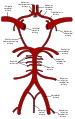

يتم تزويد المخ بالدم عن طريق 4 شرايين هي الشريانان السباتيان الغائران والشريانان الفِقريان[3]. لا يتفرع الشريان السباتي الغائر حتى يدخل الجمجمة من خلال النفق السباتي أسفل الجمجمة. بعد دخول الجمجمة يسير الشريان السباتي على شكل حرف S إلى جانب السرج التركي (باللاتينية: Sella turcica) مروراً بالجيب الكهفي (باللاتينية: Sinus cavernosus) لينقسم إلى فروعه الرئيسية:

ثم يتغير أسم الشريان السباتي الغائر ليشكل الشِّرْيانُ المُخِّيُّ الأَوسَط، هذا الشريان الذي يعتبر امتداداً للشريان السباتي الغائر، والذي يزود الجزئين الجانبيين من الدماغ.